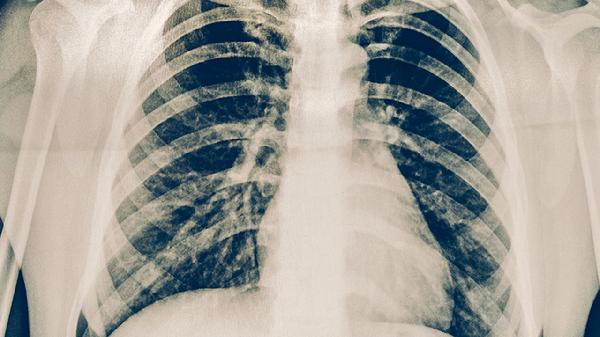

肺炎有糖尿病应该吃点儿什么东西

肺炎患者合并糖尿病时,可以适量吃西蓝花、燕麦、鸡蛋、苹果、鱼肉等食物,也可以遵医嘱使用阿莫西林胶囊、盐酸二甲双胍片、格列美脲片、氨溴索口服溶液、胰岛素注射液等药物。建议及时就医,积极配合医生治疗,在医生的指导下服用合适的药物,并做好饮食调理。

肺炎合并糖尿病患者需要特别注意营养均衡与血糖控制的双重管理。饮食上坚持低糖、低脂、高蛋白原则,少食多餐,避免血糖大幅波动。烹饪方式以蒸、煮、炖为主,限制油炸食品。保证每日充足水分摄入,肺炎急性期可适当增加蛋白质比例。同时要规律监测血糖,遵医嘱调整降糖方案。适当进行呼吸功能锻炼,如腹式呼吸操,但避免过度劳累。保持居室空气流通,注意保暖防寒。如出现持续高热、呼吸困难或血糖难以控制等情况需立即就医。